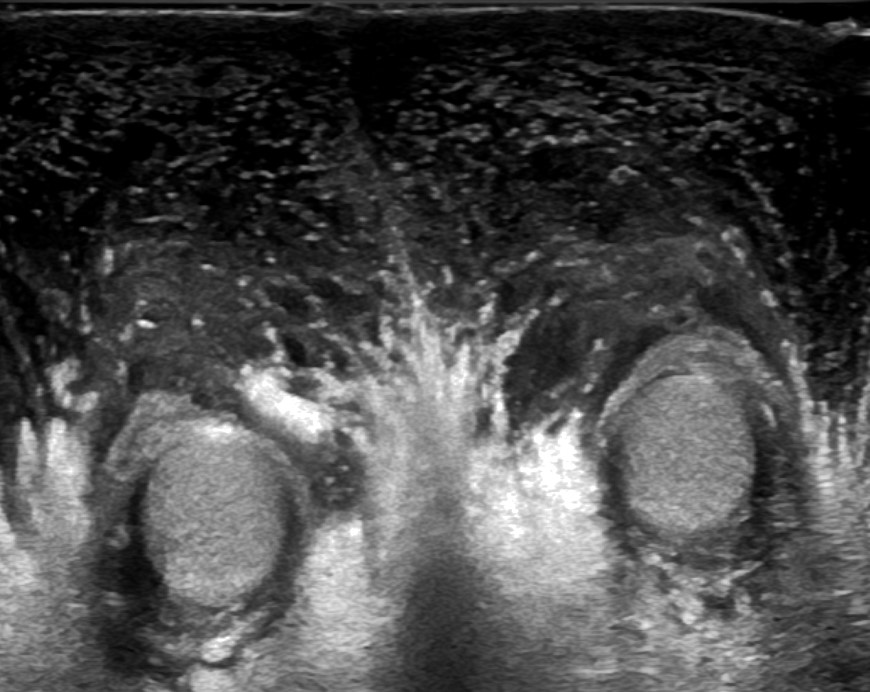

A 7-year-old boy, with no significant medical history, was admitted with complicated acute appendicitis and underwent an appendectomy. Two days after surgery, he developed painless, marked scrotal swelling. Physical examination revealed significant scrotal edema and erythema without tenderness. Ultrasound (US) showed diffuse hypoechoic thickening of the scrotal wall and pronounced subcutaneous edema, while the testes and epididymis appeared normal (Figure 1). Doppler imaging demonstrated marked bilateral hypervascularity in the scrotal wall, including the "fountain sign" (Figure 2), with normal intratesticular blood flow (Figure 3). These findings were consistent with acute idiopathic scrotal edema (AISE). The patient was managed conservatively with anti-inflammatory and antihistamine medication. The edema entirely resolved after four days, and a follow-up US confirmed the resolution of hypervascularity and edema.

Figure 1: Transverse US scan showing diffuse thickening of the scrotal wall and pronounced subcutaneous edema, with unremarkable testes and epididymis.

From a radiological perspective, the diagnosis of AISE is often established using US, which is the modality of choice due to its non-invasive nature and high sensitivity for scrotal pathology.2 US findings typically include diffuse thickening of the scrotal wall and marked subcutaneous edema, with unremarkable testes and epididymis.1,2 Doppler imaging can further confirm the absence of testicular torsion by demonstrating normal intratesticular blood flow.3 A distinctive feature observed on Doppler imaging in AISE is the "fountain sign", characterized by hypervascularity in the scrotal skin and dartos fascia, due to increased flow in the anterior and posterior scrotal arteries.3 This sign is considered a hallmark of AISE. It helps to differentiate it from other causes of acute scrotal swelling, such as epididymitis, orchitis, torsion of the appendix testis or testicular torsion, which usually present with more severe clinical symptoms and abnormal testicular findings on imaging.3